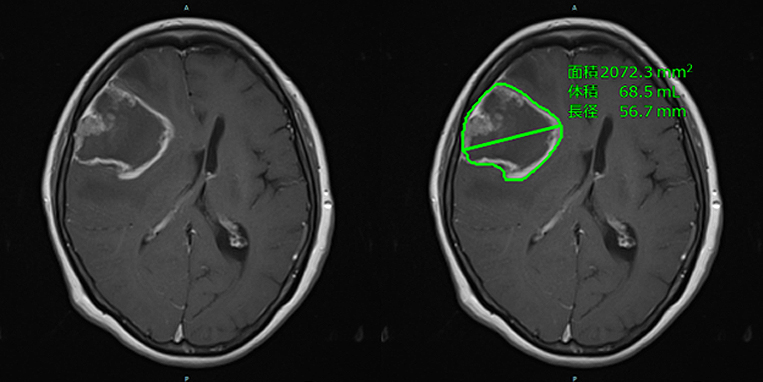

がん患者さんのフォローアップのために定期的に撮影する経時的なCT画像を用いて位置合わせを行い、差分の画像から脊椎・脊柱管の形状を踏まえた情報を用い、腫瘍の脊柱管内への浸潤の可能性がある領域の可視化を支援することができる。

図)脊椎の転移性骨腫瘍のCT差分画像

a. 前回のCT画像。

b. 今回のCT画像。

c. 今回と前回のCT画像を用い、脊柱管内の差分領域を表示。

d. 撮影範囲全体の椎体での解析結果を一覧表示。

下段中央画像(c)の黄色領域。脊柱管内の差分結果により浸潤の疑いがある領域の可視化を支援

(画像は研究中のもの)